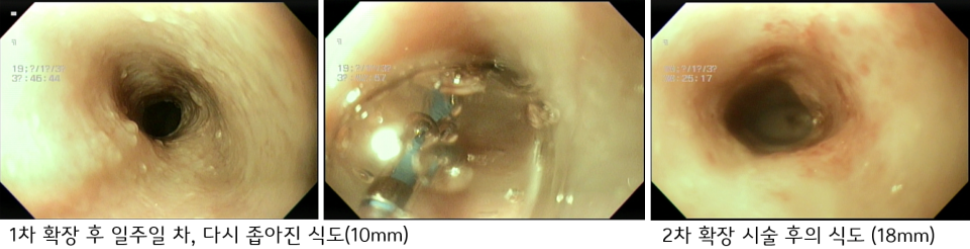

1차 확장 시에는 환자의 식도가 6mm에서 1mm 단위로 12mm 까지 확장을 진행하였습니다.

좌측 사진 - 확장 전의 식도 (6mm) / 우측 사진 - 1차 확장 시술 후의 식도 (12mm)

1차 확장술 이후 환자는 유동식 식이가 가능하였으나 아직 덩어리진 식이는 하지 못하였습니다.

식도 확장술 후 손상된 식도가 회복하면서 식도는 다시 일정부분 좁아지므로 다시 여러 차례의 단계적 확장 시술이 필요합니다.

2차 확장술 이후 환자는 고구마 등 덩어리진 식이가 가능해졌고 3차 확장술에서는 기존에 비하여 직경의 감소가 뚜렷하지 않았습니다.